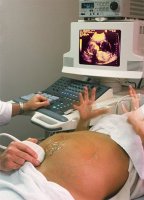

На сроке 20-22 недели уже можно отчетливо определить движения плода. Очень часто будущие родители получают на руки диск, записанный в ходе проведения УЗИ. На этом этапе внутриутробного развития происходит формирование внутренних органов, систем и костного скелета. Плод уже полностью похож на маленького человечка, на головке у будущего малыша появляются волосы, становятся заметными ногти на пальчиках рук и ног.

Второе УЗИ позволяет определить, насколько правильно развиваются пропорции тела плода и его масса. Есть нормы, которые определяются при помощи ультразвукового исследования. На сроке 20-22 недели вес эмбриона составляет 250-300 г, а рост колеблется в пределах 16-18 см.

Внутренние органы плода на этом сроке начинают работать активнее, происходит формирование подкожно-жировой клетчатки. Нервная система развита уже на таком уровне, что малыш чувствует и реагирует на прикосновения. Во время ультразвукового исследования можно увидеть, как плод двигается в полости матки, держится ручкой за пуповину, подносит ко рту пальчик.

Во время проведения второго УЗИ, кроме работы внутренних органов и двигательной активности, можно также увидеть мимику будущего малыша, сосчитать количество пальчиков и определить его пол.